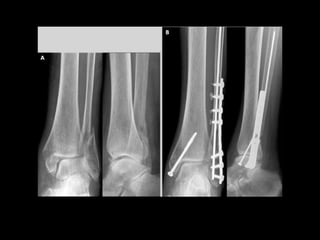

LES MEMBRES INFÉRIEURS

2. ARTHROLOGIE